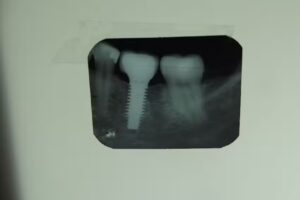

Un caso frecuente en los comentarios es el de pacientes que llegan con ausencia de varias piezas y salen con rehabilitaciones completas mediante implantes dentales combinados con coronas de porcelana. Este tipo de tratamientos suele requerir planificación previa, estudios radiográficos y varias sesiones, y los usuarios describen que el equipo se toma el tiempo de explicar alternativas, costos, tiempos de recuperación y cuidados posteriores, lo que aporta confianza y sensación de acompañamiento a lo largo del proceso.

El área de implantes dentales parece ser uno de los pilares de la propuesta de Dental Total, tanto a nivel de la red como en la sucursal de Pacheco 2. Los implantes se utilizan para reemplazar piezas perdidas y, según la propia información de la marca, permiten colocar coronas que se ven y funcionan como dientes naturales, evitando desgastar piezas sanas adyacentes. Pacientes que se realizaron uno o varios implantes señalan resultados estéticos satisfactorios y una mejora notable en la funcionalidad al masticar, siempre que se sigan las indicaciones postoperatorias y los controles recomendados.